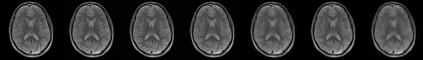

Magnetic Resonance Imaging (MRI) has excellent soft tissue contrast but is hindered by an inherently slow data acquisition process. Compressed sensing, which reconstructs sparse signals from incoherently sampled data, has been widely applied to accelerate MRI acquisitions. Compressed sensing MRI requires one or more model parameters to be tuned, which is usually done by hand, giving sub-optimal tuning in general. To address this issue, we build on previous work by the authors on the single-coil Variable Density Approximate Message Passing (VDAMP) algorithm, extending the framework to multiple receiver coils to propose the Parallel VDAMP (P-VDAMP) algorithm. For Bernoulli random variable density sampling, P-VDAMP obeys a "state evolution", where the intermediate per-iteration image estimate is distributed according to the ground truth corrupted by a zero-mean Gaussian vector with approximately known covariance. To our knowledge, P-VDAMP is the first algorithm for multi-coil MRI data that obeys a state evolution with accurately tracked parameters. We leverage state evolution to automatically tune sparse parameters on-the-fly with Stein's Unbiased Risk Estimate (SURE). P-VDAMP is evaluated on brain, knee and angiogram datasets and compared with four variants of the Fast Iterative Shrinkage-Thresholding algorithm (FISTA), including two tuning-free variants from the literature. The proposed method is found to have a similar reconstruction quality and time to convergence as FISTA with an optimally tuned sparse weighting and offers substantial robustness and reconstruction quality improvements over competing tuning-free methods.